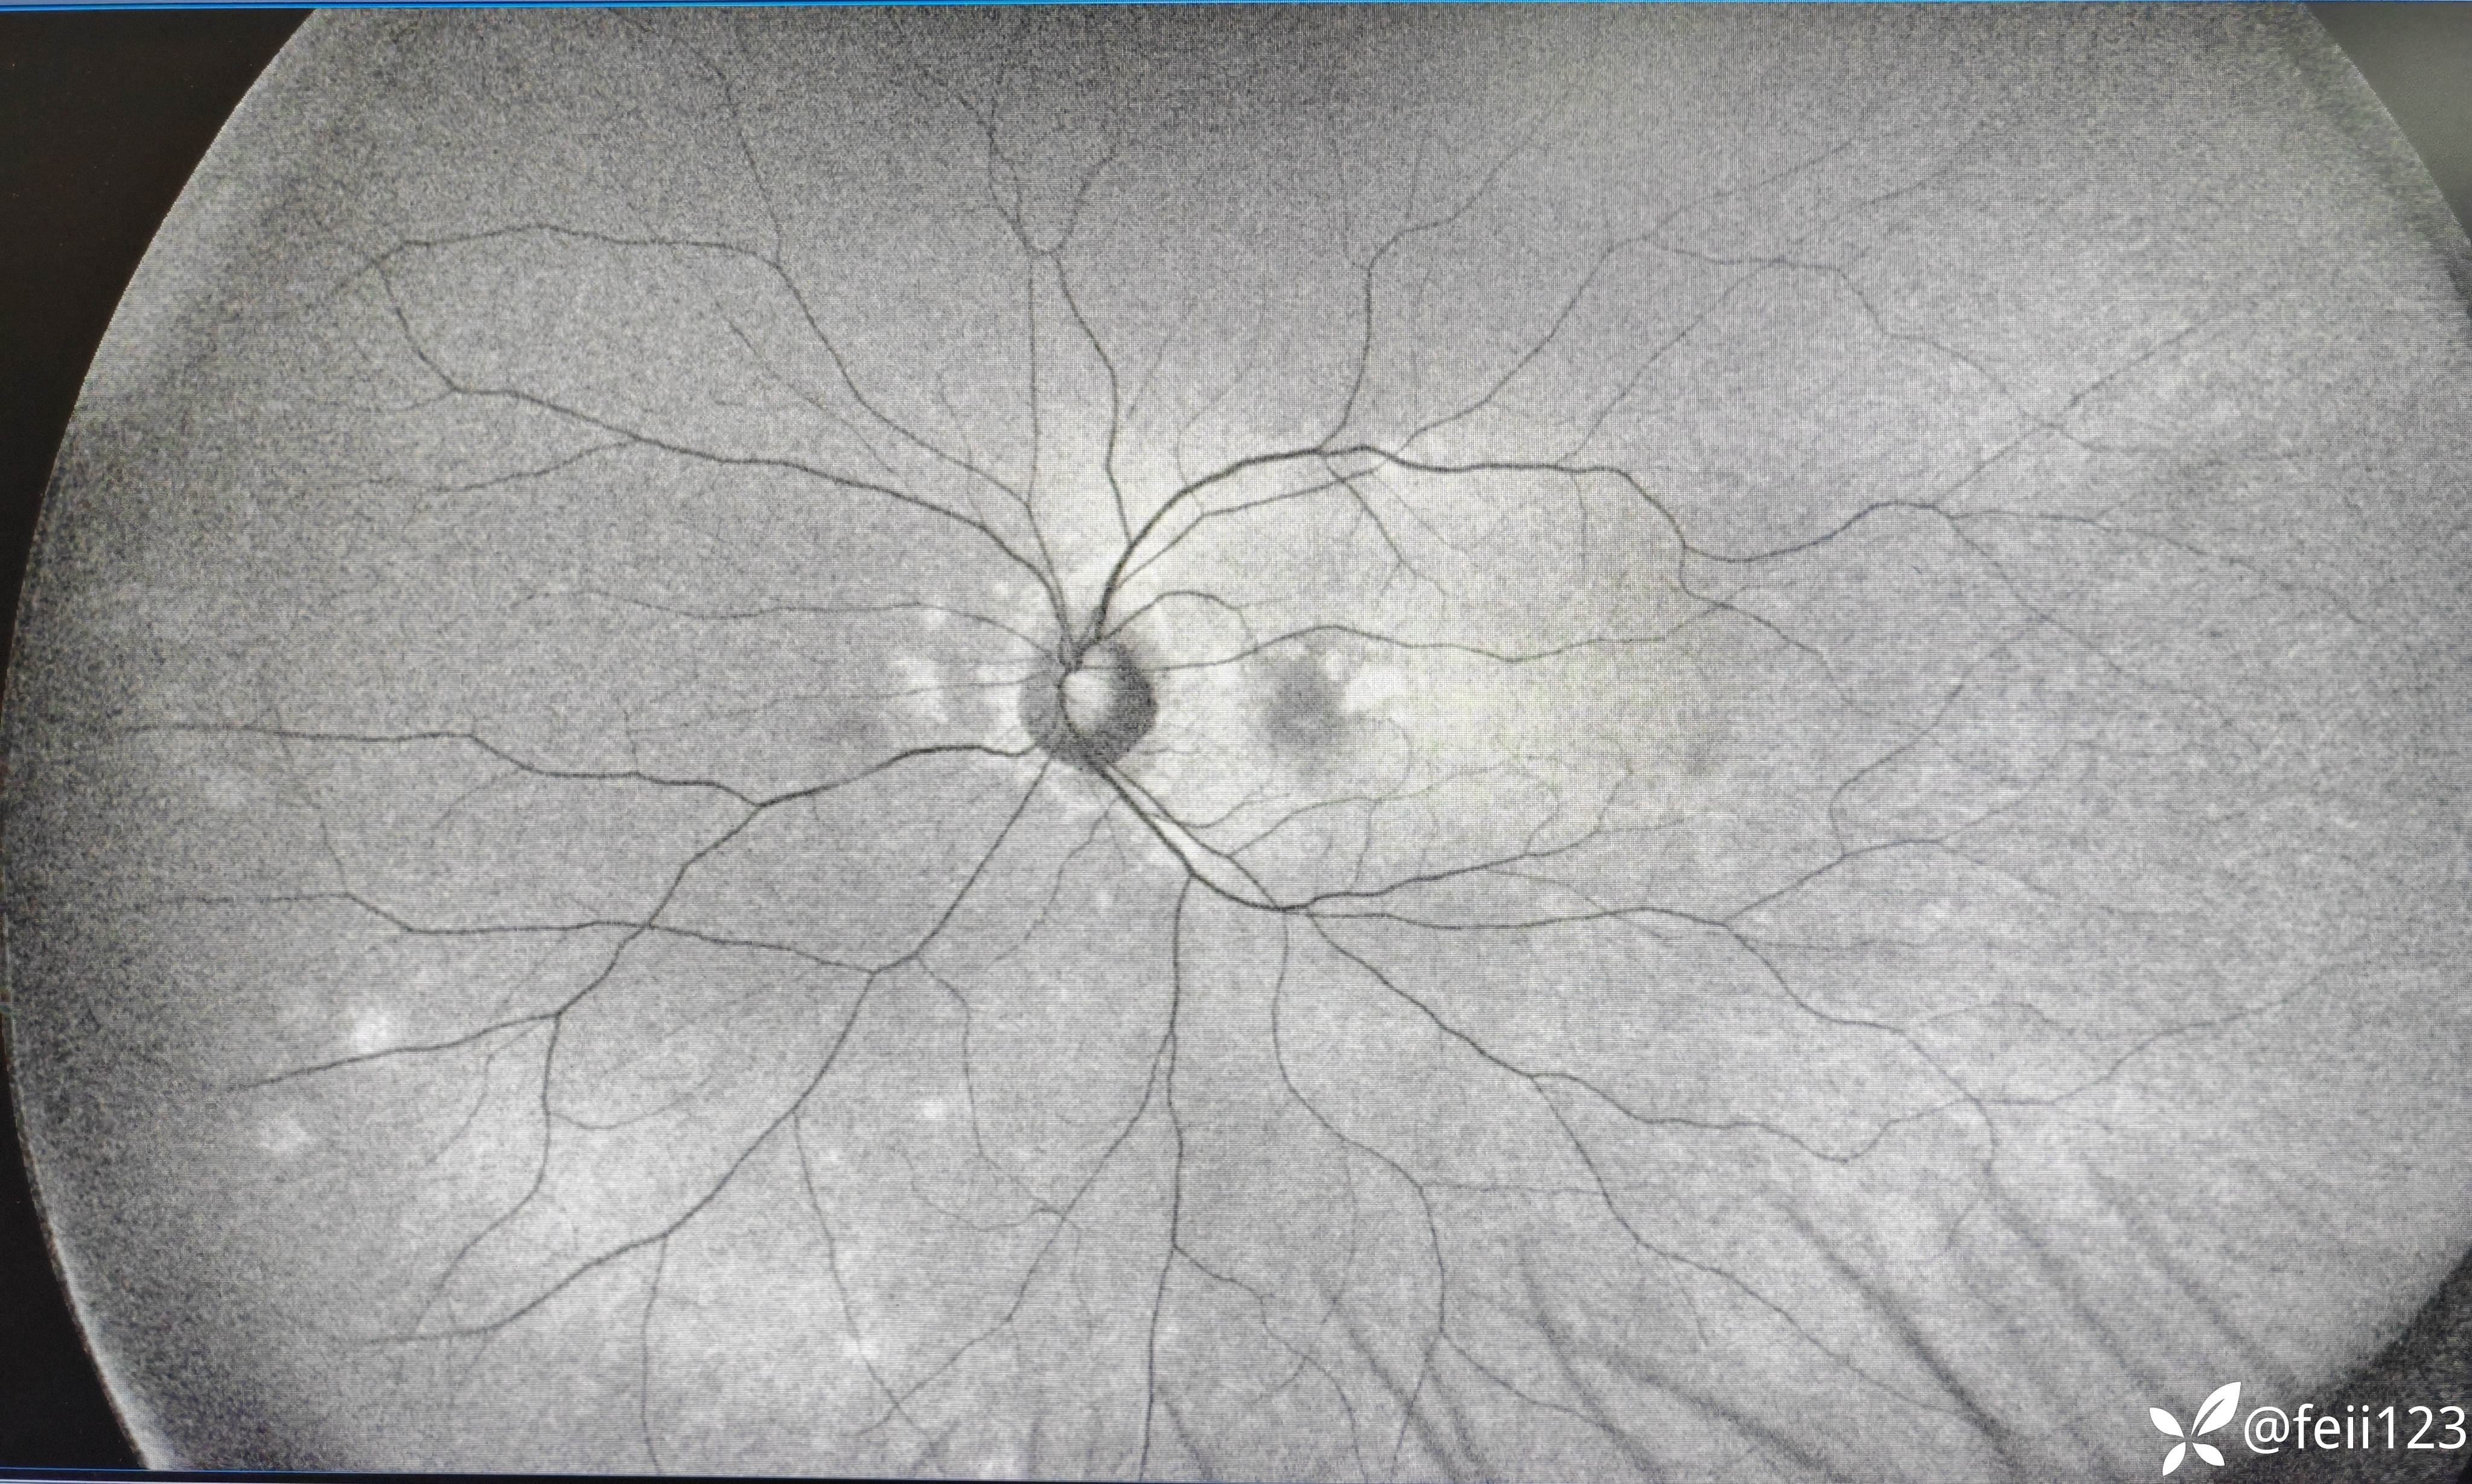

【检查】矫正视力右眼1.0左眼0.4,眼压正常15 16,眼前段未见异常,玻璃体清,眼底如图,左眼底可见后极部及鼻侧周边多个白点。